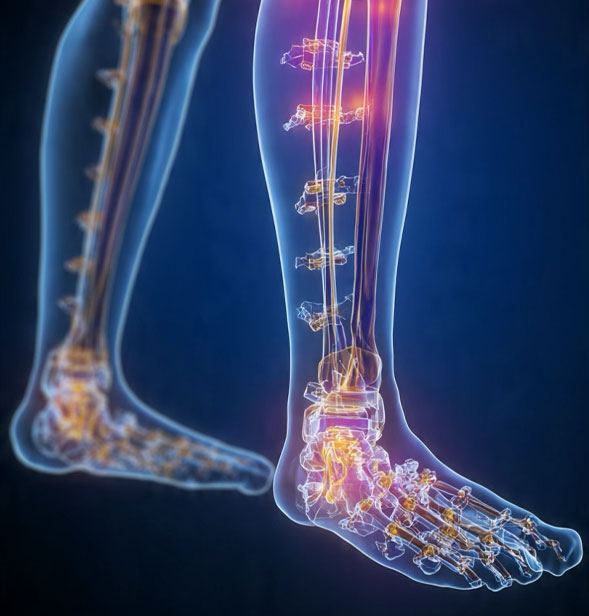

Comprehensive Orthopaedic &

Medico-Legal Musculoskeletal Care

Kyot Ortho Solutions is a specialised orthopaedic practice offering clinical musculoskeletal services and expert medico-legal orthopaedic assessments. We are committed to restoring function, improving quality of life, and providing accurate, evidence-based medical opinions for legal and insurance matters.

Our practice operates through two focused service divisions: